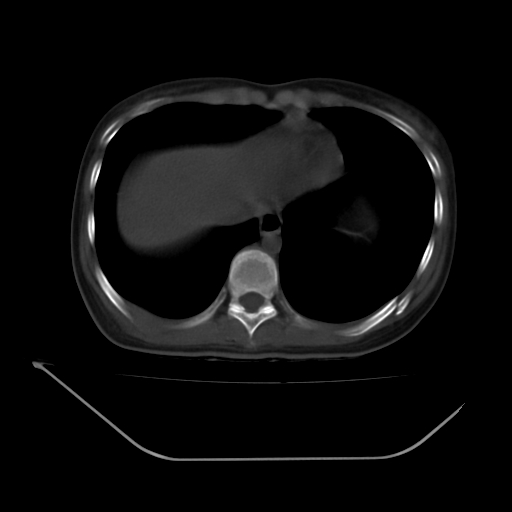

以下是引用liuyue在2008-7-19 13:02:00的发言:[br]1.肝右叶后下段及右肾挫裂伤伴腹腔积血。[br]2.右侧多发性肋骨骨折、横突骨折、右髂骨骨折伴周围软组织挫伤。[br]3.右侧腰大肌肿胀,并可见低密度影,如为气体,则肠道挫裂伤待除外。

以下是引用zhengfaming在2008-7-19 14:42:00的发言:[br]1.肝右叶后下段及右肾挫裂伤伴腹腔积血。脾脏挫裂伤待排[br]2.右侧多发性肋骨骨折、横突骨折、右髂骨骨折伴周围软组织挫伤。[br]3.右侧腰大肌肿胀,并可见低密度影,如为气体,则肠道挫裂伤待除外

以下是引用道哥在2008-7-19 16:52:00的发言:[br]肝右叶后下段及右肾挫裂伤、脾破裂伴腹腔积血。[br]2.双侧多发性肋骨骨折、横突骨折、右髂骨骨折伴周围软组织挫伤。[br]3.右侧腰大肌肿胀,并可见低密度影,如为气体,则肠道挫裂伤待除外。